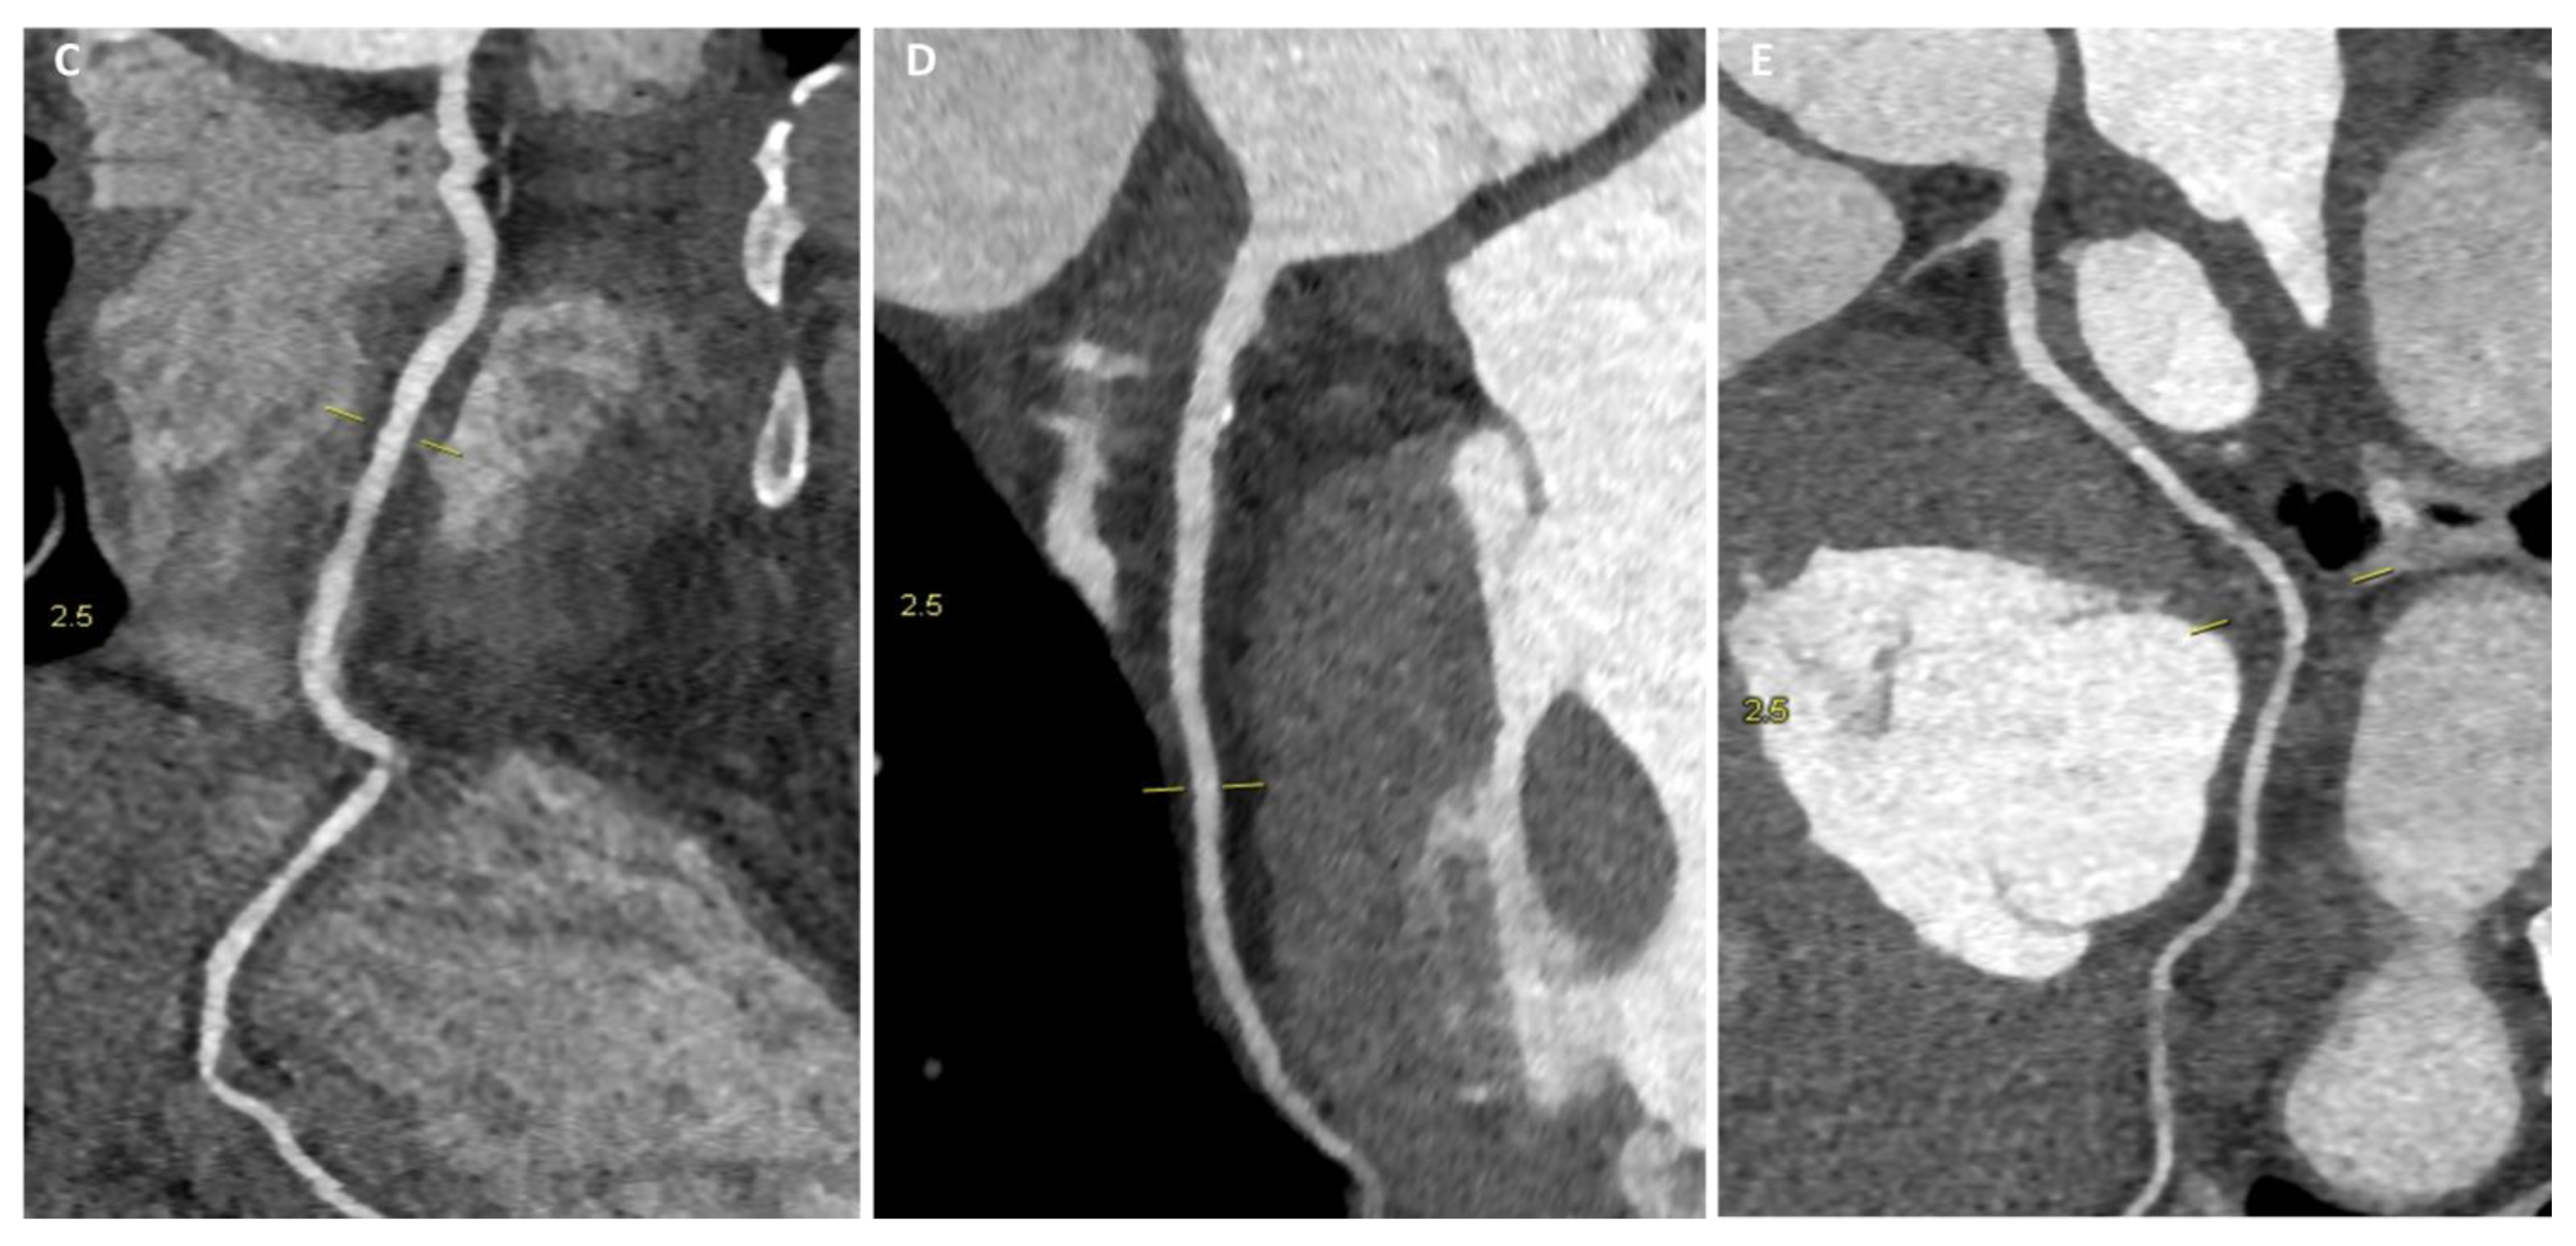

4.2.4. Cardiac Imaging: AH vs. Arrhythmogenic Cardiomyopathy

Arrhythmogenic Right Ventricular Cardiomyopathy

Left Dominant Arrhythmogenic Cardiomyopathy (LDAC)